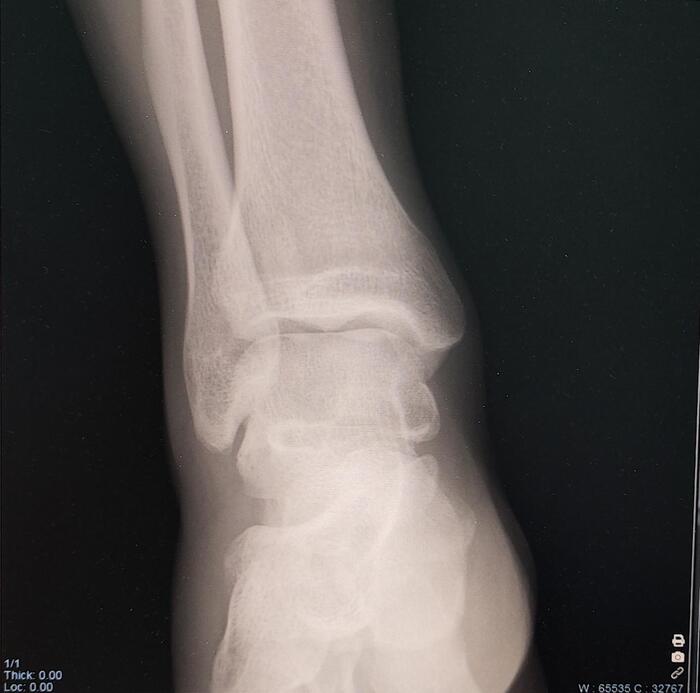

Os trigonum — это анатомический вариант развития стопы/аномалия развития, представляющая собой отдельную костную структуру, расположенную кзади от таранной кости.

• Формируется из не слившегося вторичного центра окостенения таранной кости

• Встречается у 5–15% населения, часто двусторонне.

• Может быть бессимптомной или вызывать боль при физических нагрузках, занятии спортом.

• Может вызывать задний импиджмент голеностопа — боль при тыльном сгибании стопы.

Из анамнеза-боли в левом голеностопном суставе при занятии спортом.

Описание: на Р-граммах левого гс/с в 2х проекциях суставная щель не сужена, субхондральный склероз, краевые остеофиты-не выявлены. По заднему контуру таранной кости определяется наличие дополнительной кости-os trigonum. Заключение:Os trigonum(аномалия развития левой стопы), наиболее вероятно вызывающая синдром компрессии таранной кости.

Категория годности с диагнозом Os trigonum(аномалия развития левой стопы), наиболее вероятно вызывающая синдром компрессии таранной кости-по статье 69г Б3-годен к военной службе с незначительными ограничениями.